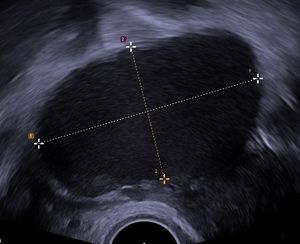

질식 초음파 검사로 촬영한 67 x 40 mm 크기의 자궁내막종으로, 다소 과립상의 내용물을 보입니다. - 난소에 생긴 자궁내막증으로 인한 것이다.

난소 낭종은 보통 초음파, CT 촬영, MRI 중 하나를 통해 진단한다.[13] 초음파는 가장 중요한 영상 기법인데, CT 촬영에서 이상 소견이 발견되더라도 초음파에서는 정상으로 나타나는 경우가 있기 때문이다.[4][6] 다른 영상 기법이 필요한 경우, MRI가 CT 촬영보다 더 신뢰할 수 있다.[4] 경험이 풍부한 초음파 검사자는 대개 양성 난소 낭종을 쉽게 식별할 수 있으며, 다른 접근 방식에 필적하는 정확도를 보이기도 한다.[4]